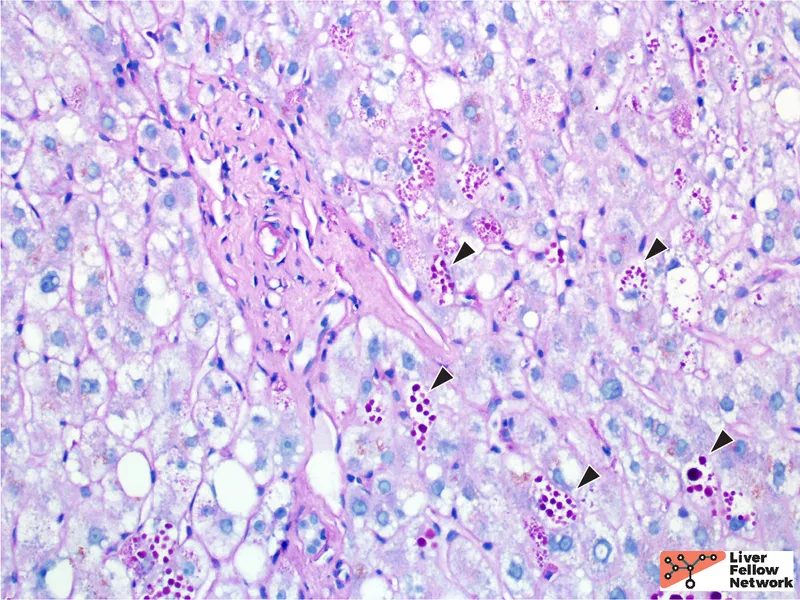

- Liver biopsy: ↑ Iron (Perls' Prussian blue stain); quantification of hepatic iron concentration.

- Hereditary Hemochromatosis: HFE gene (C282Y), iron overload, ↑ ferritin, ↑ transferrin saturation, Prussian blue.